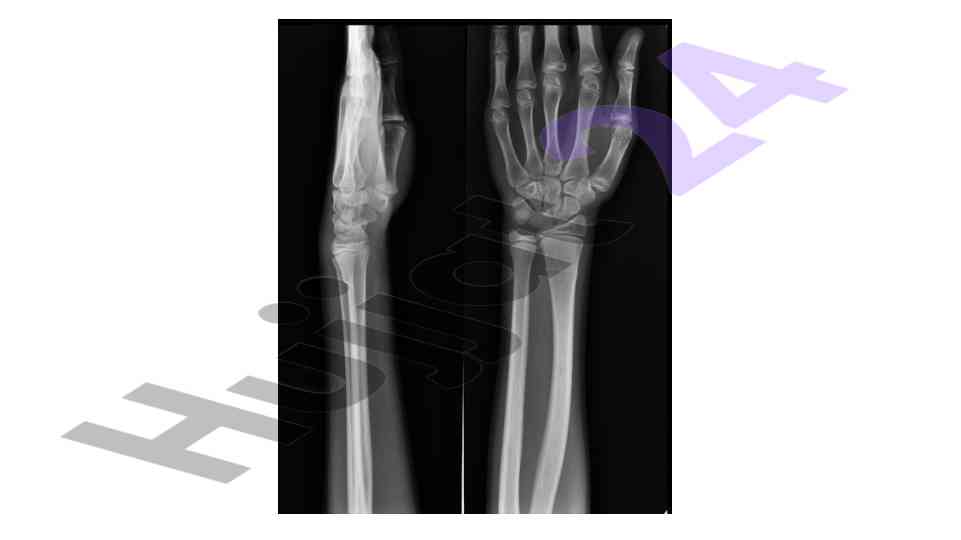

Muskuloskeletal system in pediatrics

An overview of the muskuloskeletal system with a focus on pediatric applications and implications for treatment.